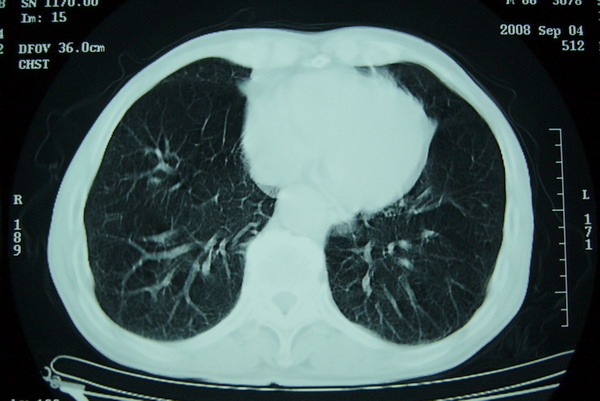

右上周围型肺癌,慢支,肺气肿。

分叶及少量边缘性钙化,老年人,周围性肺癌首先考虑。

右上肺一不规则团块,边缘有分叶和毛刺,纵隔有淋巴结肿大。右肺周围性肺癌首先考虑。